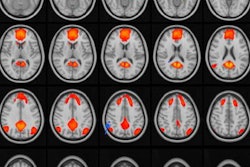

Axial nonenhanced CT (A) demonstrates no acute intracranial abnormality in a patient with left frontal calvarial fracture. Axial T2-weighted GRE MRI (B) reveals subarachnoid hemorrhage of the left frontal lobe (white arrow). Images courtesy of co-authors Drs. Daniel Lindberg and David Mirsky."Subjectively, radiologists felt that identification of skull fractures became easier over time with experience comparing CT with fast MRI," the authors wrote. "We recommend that fast MRI implementation begin with children who require repeat imaging for TBI identified by CT to provide a training period in which traumatic injuries can be compared on the two modalities."